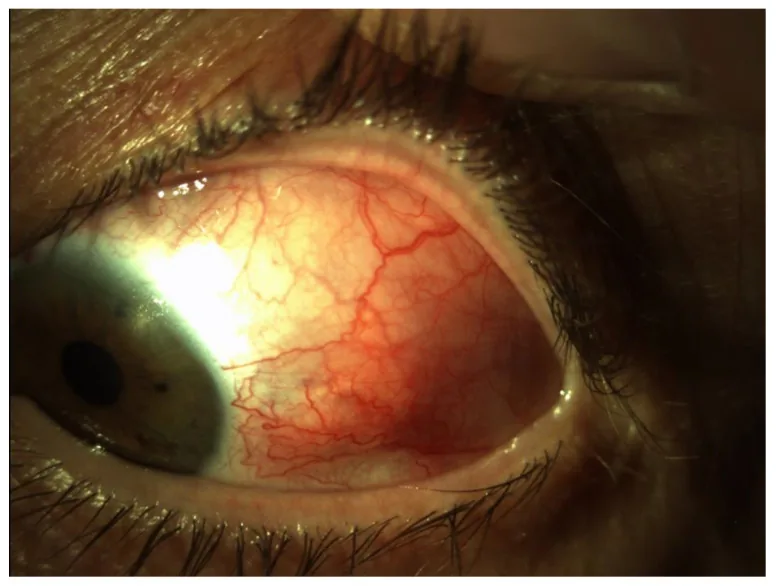

びまん性強膜炎

| 前部強膜炎 | びまん性 | 最多。強膜血管の拡張と蛇行によるびまん性充血 |

Section titled “臨床所見(医師が診察で確認する所見)”- 深在性血管の拡張と蛇行:強膜血管の炎症により、上強膜血管叢と強膜内血管叢が拡張する。強膜血管には可動性がない。

- 紫青色の色調:強膜炎に特徴的な色調変化である。結膜炎や上強膜炎の鮮赤色とは対照的であり、暗赤色〜紫青色を呈する。細隙灯顕微鏡よりも自然光下の肉眼観察のほうが把握しやすい。長期罹患例では限局性・びまん性の強膜菲薄化により青黒く観察される。

Section titled “4. 診断と検査方法”- 自然光下の肉眼観察:結膜炎や上強膜炎の鮮赤色の充血に対し、強膜炎では暗赤色〜紫青色を呈する。長期罹患例では強膜菲薄化により青黒く観察される。これらの色調変化は細隙灯顕微鏡よりも明室での肉眼観察のほうが把握しやすい。

- 細隙灯顕微鏡検査:強膜血管の拡張・蛇行、結節の有無、強膜結節の暗赤色所見、菲薄化、壊死、穿孔を評価する。眼瞼結膜には炎症所見を認めない点が結膜炎との鑑別点となる。